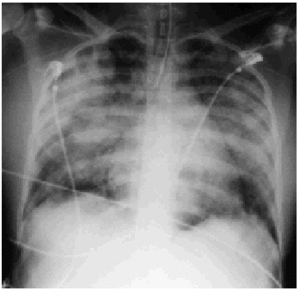

La radiografía de tórax mostraba un infiltrado alveolar bilateral con una silueta cardíaca normal (fig. 1). El electrocardiograma evidenciaba un ritmo sinusal de 106 lat/min, con descenso del ST difuso en la cara anterior y lateral. La ecografía abdominal informaba de un parénquima hepático de estructura homogénea con dilatación de las suprahepáticas con flujo dentro de la normalidad y una mínima cantidad de líquido libre perihepático y en la pelvis. La vesícula biliar evidenciaba paredes ligeramente engrosadas. No había dilatación de las vías biliares intra y extrahepáticas. El bazo era de tamaño grande y los riñones, de características normales

Figura 1. Radiografía de tórax anteroposterior realizada en el ingreso donde se aprecia infiltrado alveolar bilateral, con silueta cardíaca normal.